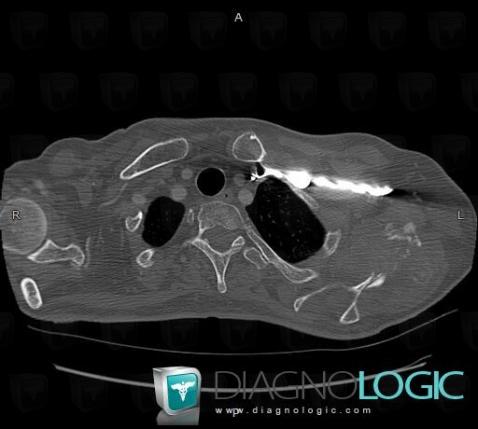

Metastasis, Scapula, CT

Here is the specific information in the key image above:

- Diagnosis Metastasis, Location(s) Scapula, with gamuts Ill-defined osteolysis, Cortical osteolysis